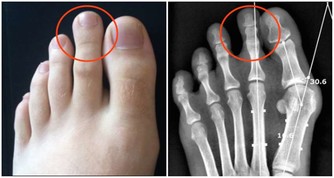

膝蓋關節一直是諸多長輩的困擾,尤其到了中老年又缺乏運動的情況下,

很容易伴隨著天氣或者其他原因而不適...